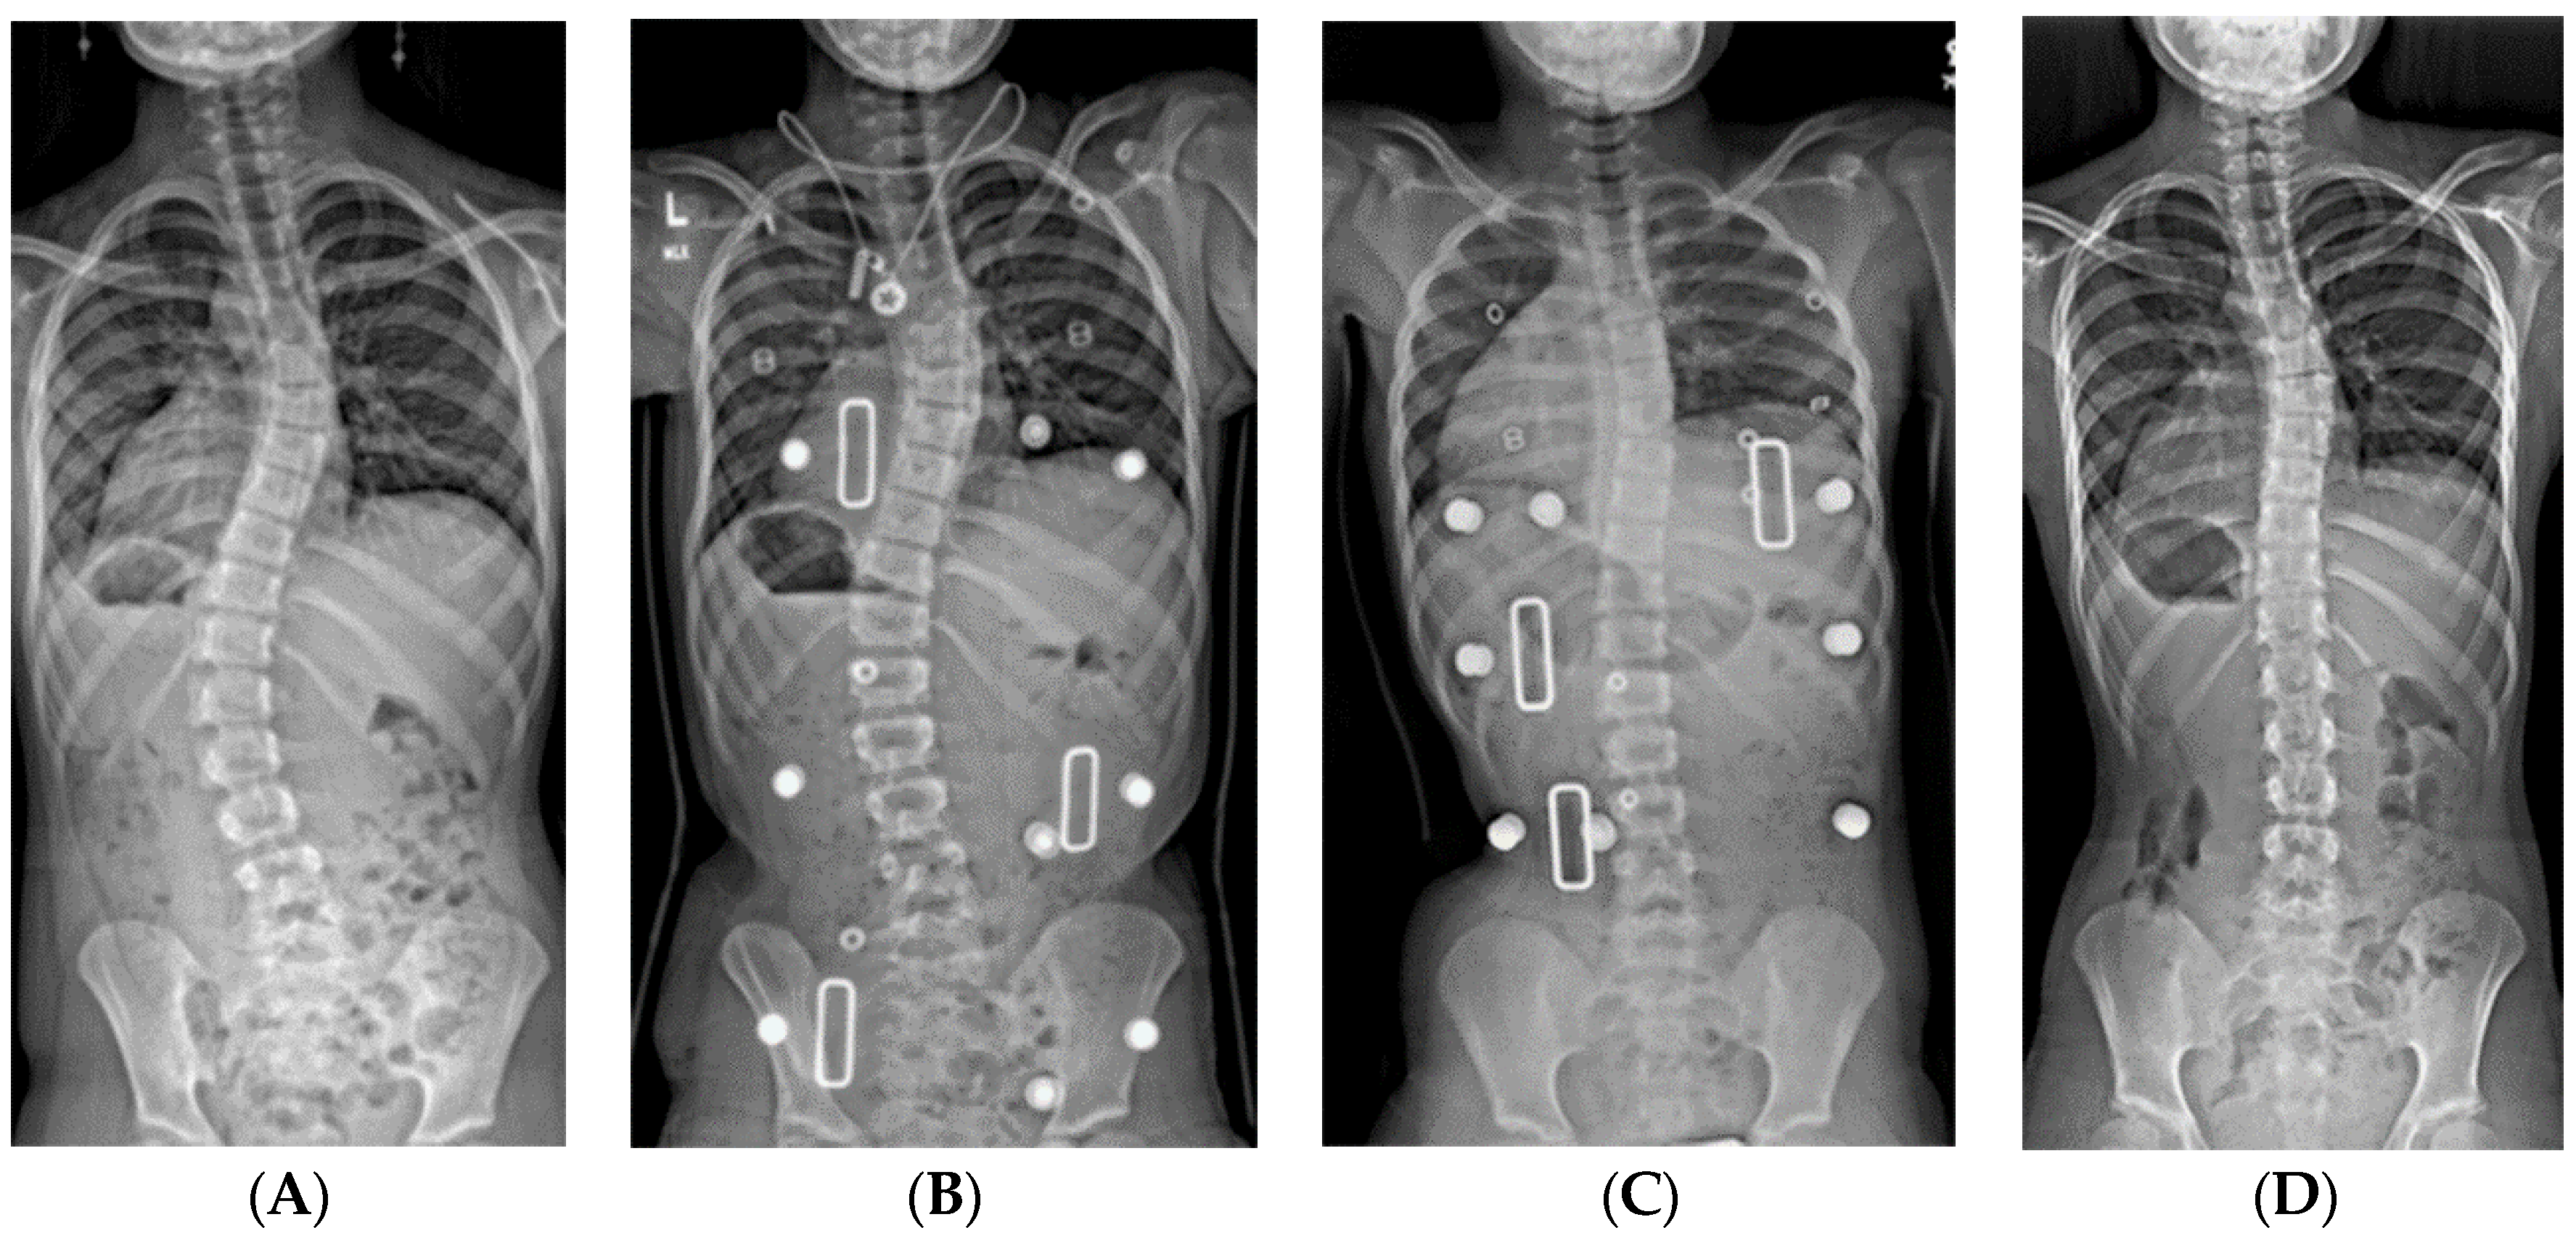

Figure 4.

(A) 18-month-old female with PWS deletion type with 106° curve. (B) Same patient at 18 months old, sitting in first cast, 54° curve. (C) AP and lateral views of spine at 6 years old, after 18 casts, 61° curve, just prior to surgery. (D) AP and lateral views of spine 4 months after placing magnetically actuated spine rods T3–L3. Curve was corrected to 30°, maintaining her pre-operative kyphosis. (E) AP and lateral views of spine at 10 years old, just prior replacement with new expandable rods. Due to adding on, curve measures 50°, which was addressed by including L4 in the construct.

Oore et al. reported the only published series of serial casting for children with PWS, noting a reduction of curve size in their ten patients, from 45° to 37° [40]. We reviewed our results from 34 children with PWS with more than 24 months’ follow-up after their initial spine cast. The average age at initial casting was 32 months (range 14–64 months) with an average of 8 casts (range 3–18). Twelve children (35%) were in the “cured” group; all were weaned out of brace at one year after completion of casting. Seven of these patients had maternal disomy 15, five had the 15q11-q13 deletion, and the average initial curve was 44° (range 27°–80°). Another 18 patients transitioned to long-term brace wear (10 with deletion, 7 with maternal disomy 15, and one having an imprinting defect). Their average initial curve of 55° (range 27°–84°) became 35° (16°–64°) at the end of casting and was 46° (27°–84°) at two years’ follow-up. Four patients with severe initial curves (54°, 84°, 95°, and 106°) were controlled in casts until they reached a sufficient age for surgery (average 56 months old). Overall, the odds ratio for “curing” an initial curve of <50° was nine times that of a curve >50° in this cohort.

Young children with severe infantile curves may need stabilization of the spine to allow for more symmetric chest development with growth. Typically, these are child too old for spinal casting but have substantial remaining growth with curves >50° and minimal flexibility/improvement in brace. If they cannot be maintained in brace, then an expandable implant serves to internally splint the spine. Early implant versions required manual distraction, typically performed every six months as an open procedure in the operating room (Figure 8). This strategy worked well for controlling the curve and maintaining spine growth, but with the potential complications related to surgical procedures. In 2014, expandable spinal rods became available that were magnetically actuated through the skin. The rods are lengthened every three months, using an external spinning magnet, which causes the magnet within the rod to rotate thereby lengthening the rod (Figure 4). Oore et al found that the average initial curve was reduced from 76° to 42° at time of implant surgery with no change in curve size over the subsequent two years of rod elongation [40].